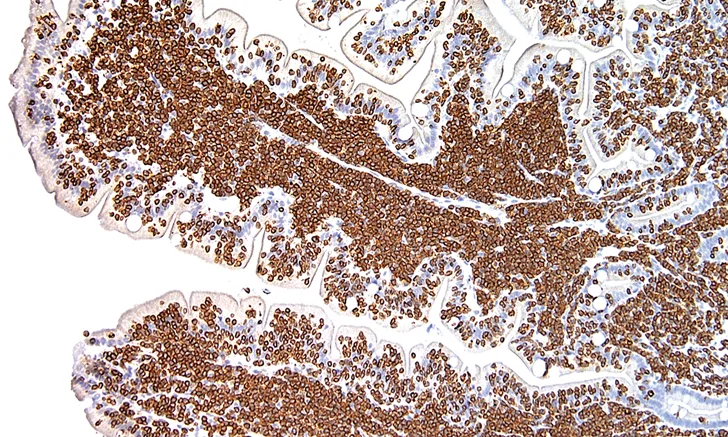

FIGURE 3 Photomicrograph of a feline small intestine biopsy showing diffuse CD3 staining (brown) identifying T-cell lymphoma

Immunohistochemistry employs antigen: antibody reactions and is used primarily by pathologists and researchers. Antibodies specific to a target of interest in the tissue are applied and detected, often using an enzymatic reaction.2 This allows pathologists to recognize certain markers in tissues, such as cytokeratin and vimentin, which identify cells of epithelial vs mesenchymal origin, respectively, and use immunohistochemistry to identify whether lymphoma is of B- or T-cell origin from a lymph node or other tissue biopsy (Figure 3). Many other specialized markers identifying specific cellular antigens can reveal further information about the tissue samples; these are the “special stains” that allow a more detailed evaluation of histopathologic biopsies.